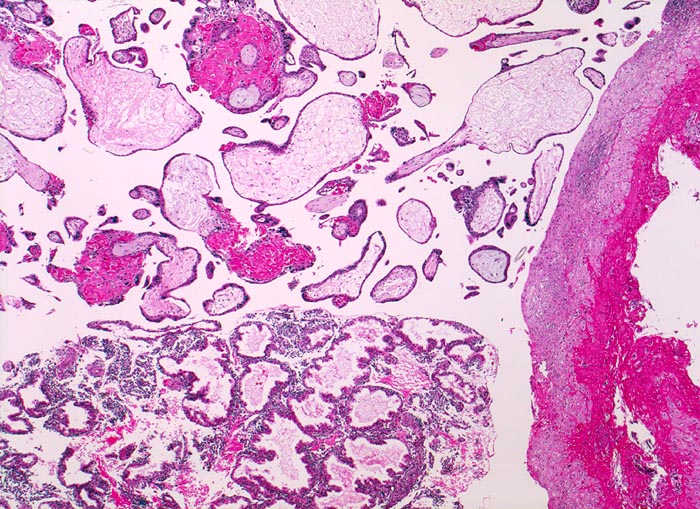

Chromosomenaberrationen verursachen nicht nur beim Feten, sondern auch an der Chorionzotte morphologisch fassbare Entwicklungsstörungen: mangelnde Verzweigungen, wandernde Trophoblastzellen im Stroma, mangelhafte Vaskularisation, hydropische Alteration des Stromas und herdförmige Atrophie oder auch Hyperplasie des Trophoblasten sind typische Befunde bei einer Chromosomenaberration. Aborte mit Triploidie zeigen in der grossen Mehrzahl das Bild einer Partialmole. Eine Tetraploidie kann das Bild einer Windmole (=Windei), einer Embryonalmole oder seltener einer Partialmole verursachen. Autosomale Trisomien können ebenfalls als Windmole oder als Embryonalmole imponieren. In nur etwa 25% aller Spontanaborte sind bei der pathomorphologischen Untersuchung ein Embryo, Embryofragmente oder ein Nabelschnuranteil nachweisbar. Die morphologische Untersuchung des Abortmaterials stellt eine wichtige Ergänzung zu den klinischen Befunden dar.

Beim ersten Abort sollte auf histologische Zeichen einer Chromosomenaberration geachtet werden. Positivenfalls sollten bei einem erneuten Abort die Weichen für eine zytogenetische Untersuchung gestellt werden. Die Wahrscheinlichkeit eines chromosomal abnormen Abortes steigt um das Doppelte, wenn bereits eine Fehlgeburt mit einer Trisomie oder Aneuploidie vorausgegangen ist und nach einem Abort mit einer Trisomie, gleichgültig welches Chromosom betroffen ist, liegt das Risiko für die Geburt eines lebenden Kindes mit Trisomie 21 zehnmal höher als in der Allgemeinbevölkerung. Aborte mit normalem Chromosomensatz zeigen meist auch im Wiederholungsfall einen normalen Chromosomensatz. Die histologische Untersuchung des Abortmaterials hilft deshalb bei der gezielten Indikationsstellung für weitergehende aufwändige zytogenetische Abklärungen bei den Eltern bzw. am Abortmaterial. Eine Abgrenzung der Partialmole ist klinisch von Bedeutung, da die Partialmole, wenn auch selten (ca. 5%), in eine invasive Mole, eine metastasierende Mole oder in ein Chorionkarzinom (Einzelfälle) übergehen kann. Eine Verlaufsbeobachtung der beta-HCG Werte ist deshalb nicht nur bei einer kompletten Mole, sondern auch bei einer Partialmole angezeigt.

Aufgabe der histologischen Untersuchung des Abortmaterials ist zum einen die Bestätigung der intrauterinen Lage der Schwangerschaft zum Ausschluss einer Extrauteringravidität. Zum anderen soll die histopathologische Untersuchung soweit als möglich zur Klärung der eigentlichen Abortursache beitragen. Vor allem müssen die therapeutisch relevanten Partialmolen und kompletten Blasenmolen histologisch diagnostiziert werden. Zwar kann die histologische Untersuchung den Verdacht auf eine chromosomale Aberration erwecken, doch ist zu deren Bestätigung eine Flowzytometrie, eine Karyotypisierung, Comparative Genomische Hypridisierung oder Fluoreszenz in Situ Hybridisierung erforderlich und sinnvoll. Der Verdacht auf eine Koagulopathie soll zur Abklärung der mütterlichen Gerinnungsparameter führen. Am Paraffinmaterial ist der gezielte Nachweis einer Mutation möglich, z.B. von Faktor V Leiden.

• Vergrösserte Plazentarzotten mit hydropischem Zottenstroma.

• Vereinzelt Zytotrophoblasteinschlüsse im Stroma.

• Vorwiegend einschichtiges Zytotrophoblastepithel ohne Atypien und mehrkerniger Synzytiotrophoblast. Physiologische polare Trophoblastproliferate.